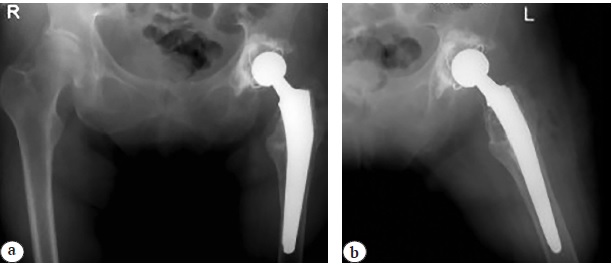

A 70-year-old patient presented to the Ural Clinical Therapeutic and Rehabilitation Center named after V.V. Tetyukhin (Nizhnii Tagil) with complaints of pain and limited movements in the left hip joint. Her medical history showed that five years ago she had undergone osteosynthesis of the neck of the left femur with a bundle of wires at the local central district hospital in Perm region. Three years later, a progressive pain syndrome in the area of intervention occurred. On presentation to the health care facility where the primary surgery had been performed, femoral neck pseudarthrosis and K-wire fracture and migration were diagnosed. Patient was admitted to the hospital, and elective surgery for removal of fixators was performed. However, the broken wire could not be removed for technical reasons. Wound having been healed, the patient was discharged for outpatient treatment. During the next two years, a mild pain syndrome persisted, but the patient was not followed up by an orthopedic traumatologist. Over the past 6 months, the pain increased, which was the reason for the patient's reapplication for medical care. Plain X-ray of the pelvis was performed and showed wire migration into the abdominal cavity (Fig. 1 a). At the time of examination, there was no evidence of abdominal organ damage. The patient was urgently referred to the admission department of the Ural Clinical Therapeutic and Rehabilitation Center named after V.V. Tetyukhin, where a CT scan of the abdomen was performed and the localization of the foreign body was determined (Fig. 1b).

Fig. 1. Plain X-ray of the pelvis (a) and CT scan (b) at admission to hospital: fracture and K-wire migration